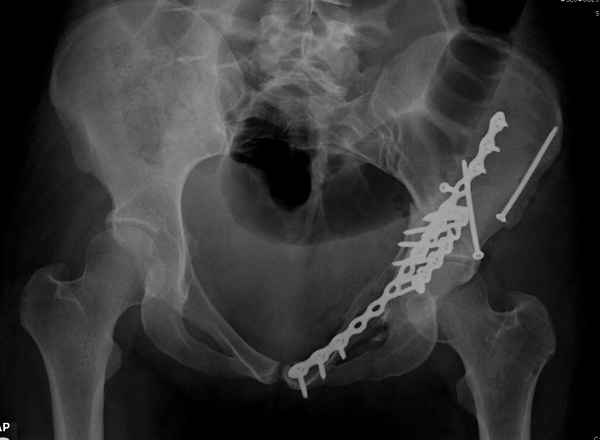

высылаю дополнительно сканы.

Когда перелом не получается отнести к какому либо типу - эффективнее всего описать более детально. В дальнейшем проще бывает сортировать, и что важнее - "руководство к действию" бывает более обоснованным. В данном случае графа клинического диагноза может выглядеть так: Застарелый разрыв правого крестцово-подвздошного сочленения, консолидирующиеся со смещением переломы крыла и тела правой подвздошной кости, обеих колонн и задней гемисферы правой вертлужной впадины. Состояние после остеосинтеза.

Судя по представленным реконструкциям (не очень хорошего качества - много наводок)

мы имеем дело с полупоперечным переломом у которого отломался задний край или его отломали, превратив перелом в полный двухколонный.

По отдельным срезам и тем более по реконструкции трудно судить о сращении крыла и задней колонны с осевым скелетом.

Все выступающие коллеги высказались насчет необходимости стандартных снимков по Judet, потому что для определения тактики лечения переломов вертлужной впадины 3Д снимки малоинформативны.

Из того минимума, что представлено, мне кажется, мы имеем дело с двухколонным переломом вертлужной впадины. Обычно медиальный (центральный) "вывих" головки встречаются в сложных двухколонных переломах со смещением.

Здесь несколько вариантов двухколонных свежих переломов, которые были оперированы из одного-заднего, а также из двух: переднего и заднего доступов.

Дополнительные сканы